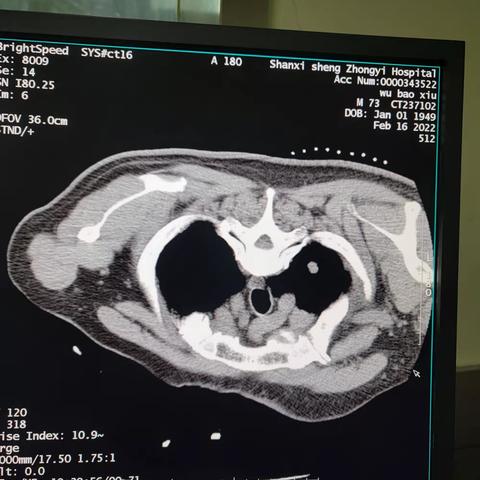

主动脉弓旁小细胞肺癌粒子植入术后纵隔血肿